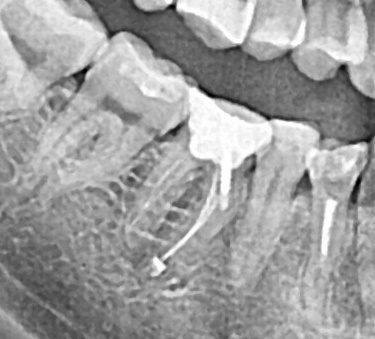

Спустя три месяца мы получили полное восстановление костной ткани. Мы установили 4 импланта в позиции 13, 14, 16, 17. Сразу были установлены формирователи десны.

Спустя три месяца вы видим отличный результат как на рентген снимке, так и на фото. Объема слизистой достаточно для начала ортопедического этапа.